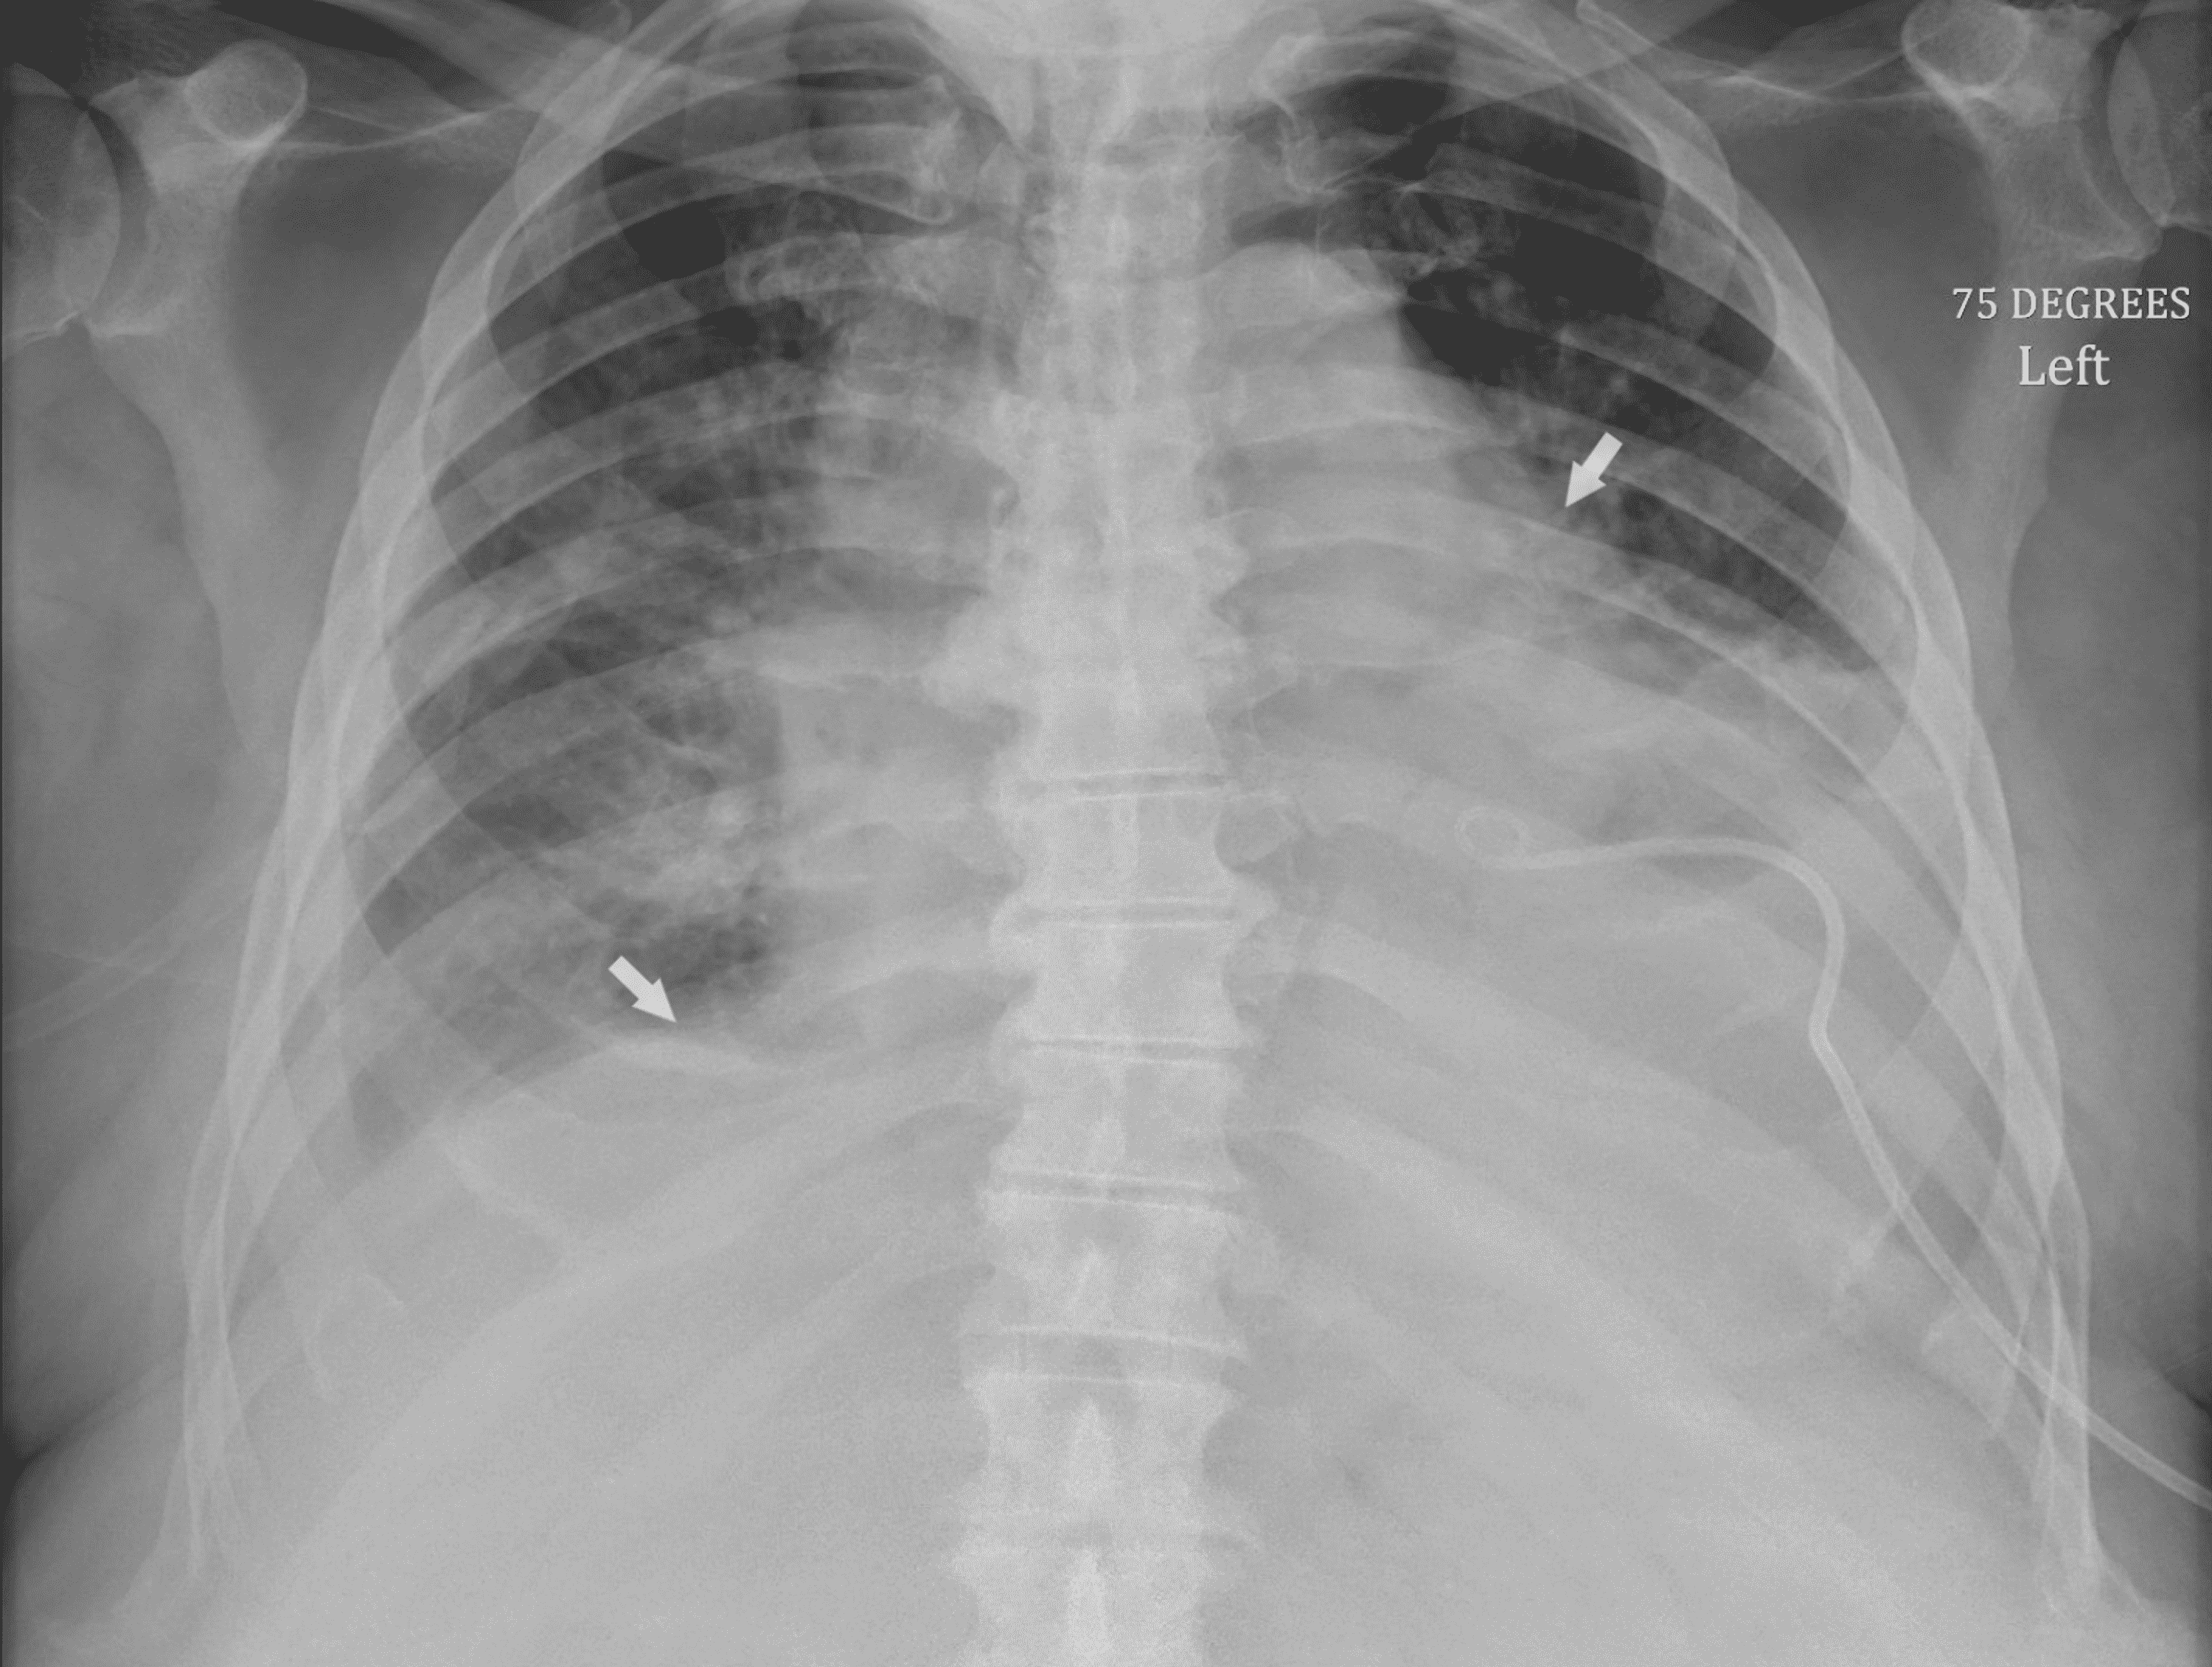

Chest X-Ray To Diagnose Leukemia . — physical exams for diagnosing leukemia. If the scan finds an abnormal. Consider seeking medical care if you have developed any of these. It is used to look for: a ct scan of the chest or abdomen can help detect an enlarged lymph node or cancers in the liver, pancreas, lungs, bones and. Although the thorax is uncommonly involved, it may occur in the lungs, pleura, mediastinum, chest. — myeloid sarcoma.

Although the thorax is uncommonly involved, it may occur in the lungs, pleura, mediastinum, chest. a ct scan of the chest or abdomen can help detect an enlarged lymph node or cancers in the liver, pancreas, lungs, bones and. — myeloid sarcoma. If the scan finds an abnormal. It is used to look for: Consider seeking medical care if you have developed any of these. — physical exams for diagnosing leukemia.

Chest X-Ray To Diagnose Leukemia Although the thorax is uncommonly involved, it may occur in the lungs, pleura, mediastinum, chest. a ct scan of the chest or abdomen can help detect an enlarged lymph node or cancers in the liver, pancreas, lungs, bones and. Although the thorax is uncommonly involved, it may occur in the lungs, pleura, mediastinum, chest. — physical exams for diagnosing leukemia. It is used to look for: — myeloid sarcoma. Consider seeking medical care if you have developed any of these. If the scan finds an abnormal.

Cureus Primary Pulmonary Hodgkin's Lymphoma A Rare Etiology of a Chest X-Ray To Diagnose Leukemia Consider seeking medical care if you have developed any of these. It is used to look for: — physical exams for diagnosing leukemia. — myeloid sarcoma. Although the thorax is uncommonly involved, it may occur in the lungs, pleura, mediastinum, chest. a ct scan of the chest or abdomen can help detect an enlarged lymph node or. Chest X-Ray To Diagnose Leukemia.

Cureus Acute Myeloid Leukemia Complicated by Hyperleukocytosis and Chest X-Ray To Diagnose Leukemia If the scan finds an abnormal. Although the thorax is uncommonly involved, it may occur in the lungs, pleura, mediastinum, chest. a ct scan of the chest or abdomen can help detect an enlarged lymph node or cancers in the liver, pancreas, lungs, bones and. — myeloid sarcoma. — physical exams for diagnosing leukemia. Consider seeking medical. Chest X-Ray To Diagnose Leukemia.

Leukemic Involvement in the Thorax RadioGraphics Chest X-Ray To Diagnose Leukemia a ct scan of the chest or abdomen can help detect an enlarged lymph node or cancers in the liver, pancreas, lungs, bones and. It is used to look for: — myeloid sarcoma. — physical exams for diagnosing leukemia. Although the thorax is uncommonly involved, it may occur in the lungs, pleura, mediastinum, chest. If the scan. Chest X-Ray To Diagnose Leukemia.